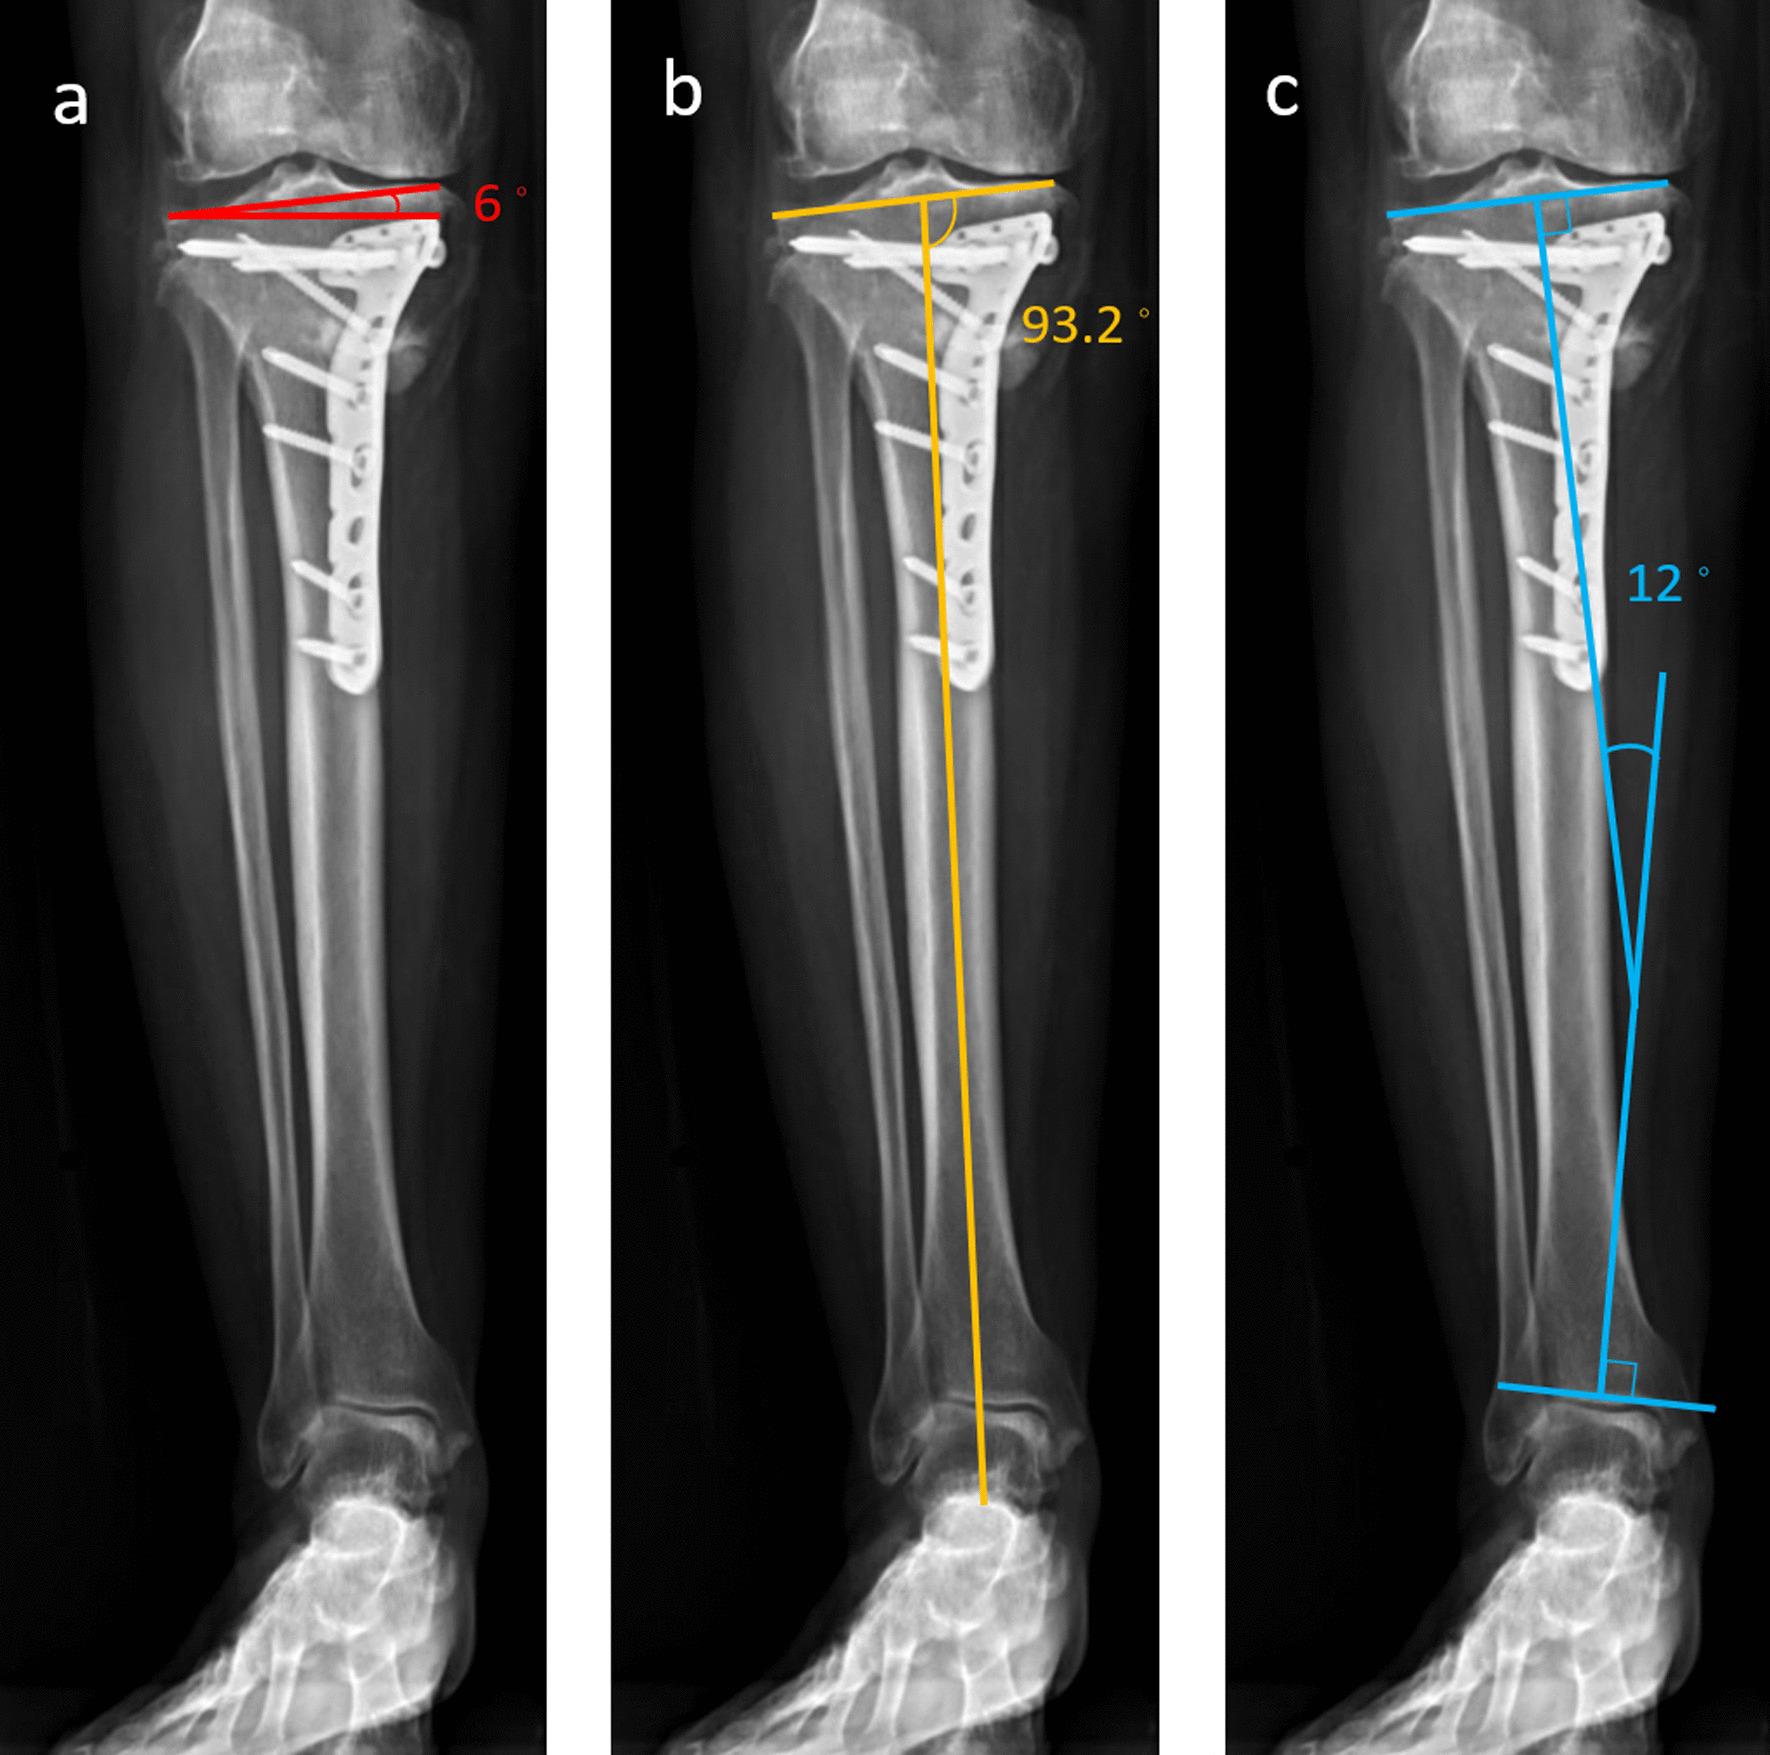

Knee-ankle joint line angle: a significant contributor to high-degree knee joint line obliquity in medial opening wedge high tibial osteotomy.

Medial opening wedge high tibial osteotomy (MOWHTO) changes the knee joint inclination in the coronal plane, which can be compensated by the ankle joint. Once there is a decompensated knee joint obliquity, it can induce excessive shear force on the articular cartilage. This study aimed to investigate the capacity of the compensation by analyzing the correlation of the knee-ankle joint line angle (KAJA) and the knee joint line obliquity (KJLO).

Ninety-six patients undergoing MOWHTO were included. We measured potential predictors including preoperative or postoperative body mass index (BMI), weight-bearing line (WBL) ratio/correction amount, knee-ankle joint line angle(KAJA), mechanical lateral distal femoral angle (mLDFA), medial proximal tibia angle (MPTA), ankle joint line obliquity (AJLO), mechanical hip-knee-ankle angle (mHKA) and joint line convergence angle (JLCA). The correlations of these predictors and postoperative KJLO were determined using Pearson correlation coefficient. The contribution of significant predictors was further analyzed using multiple linear regression. Finally, the cutoff value of the most contributing factor resulting in decompensated KJLO was derived with receiver operating characteristic (ROC) curve analysis.

RESULTS

Preoperative AJLO, JLCA, MPTA, mHKA and KJLO and postoperative KAJA and MPTA correlated with postoperative KJLO. After multiple linear regression, only preoperative AJLO and JLCA and postoperative KAJA still showed significant contribution to postoperative KJLO. Postoperative KAJA made the greatest contribution. The cutoff value of postoperative KAJA was at 9.6° after ROC analysis. The incidence rate of high-grade KJLO was 69.6% when postoperative KAJA exceeded 9.6°.

CONCLUSIONS

Postoperative KAJA is a significant contributor to high-grade KJLO after MOWHTO. The incidence was increased at angles greater than 9.6°. The results suggest that KAJA should be carefully assessed during preoperative planning or intraoperative evaluation. Postoperative KAJA < 9.6° can lower the rate of early high-degree KJLO.